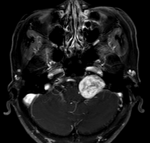

左側(cè)橋小腦角神經(jīng)鞘瘤手術(shù)術(shù)式選擇 關(guān)鍵疾?。?a href="http://m.akellydesign.com/tags/so/神經(jīng)鞘瘤-4-1.html" target="_blank">神經(jīng)鞘瘤 現(xiàn)病史【一般資料】 女性,62歲, 【主訴】 聲音嘶啞4年,左側(cè)橋小腦角占位伽瑪?shù)缎g(shù)后3年 【現(xiàn)病史】4年前患者無明顯誘因出現(xiàn)聲音嘶啞,無聽力下降,無耳痛、外耳道無膿血性等異常分泌物,偶發(fā)頭暈,無明顯頭痛,無惡心、嘔吐,視物模糊,無視物雙影,無面部歪斜,無面部及眼睛疼痛等,無明顯的下肢無力、疼痛,感覺障礙等,未予重視,3年前行頭顱MRI增強提示:左側(cè)橋小腦角區(qū)占位,在我院行伽瑪?shù)吨委煟g(shù)后3年來腫塊逐漸長大,遂就診我院頭顱MRI增強提示:左側(cè)橋小腦角區(qū)占位,大小約2.9*2.2*3.5cm,左側(cè)小...

伽馬刀治療左側(cè)橋小腦角區(qū)聽神經(jīng)瘤效果不明顯后如何調(diào)整治療方式 關(guān)鍵疾病:聽神經(jīng)瘤 現(xiàn)病史【一般資料】 男性,60歲, 【主訴】 左側(cè)橋小腦區(qū)占位伽馬刀術(shù)后3+年,左半側(cè)頭面部疼痛不適1+月 【現(xiàn)病史】患者于3年前因左側(cè)頭面部疼痛不適,于當(dāng)?shù)蒯t(yī)院就診,行伽馬刀治療,患者疼痛癥狀明顯緩解,之后未予特殊治療,1+月前患者自覺左側(cè)頭面部疼痛不適明顯加重,疼痛以額,面,枕部為主,不伴頭暈,頭痛與頭位置改變無明顯的關(guān)系,無惡心、嘔吐,無視物雙影,無面部歪斜等,左耳失聰,不伴耳鳴,無耳痛、外耳道無膿血性等異常分泌物,MRI結(jié)果示:左側(cè)橋小腦角區(qū)、內(nèi)聽道占位,考慮聽神經(jīng)瘤可能性大,病灶范圍較前...